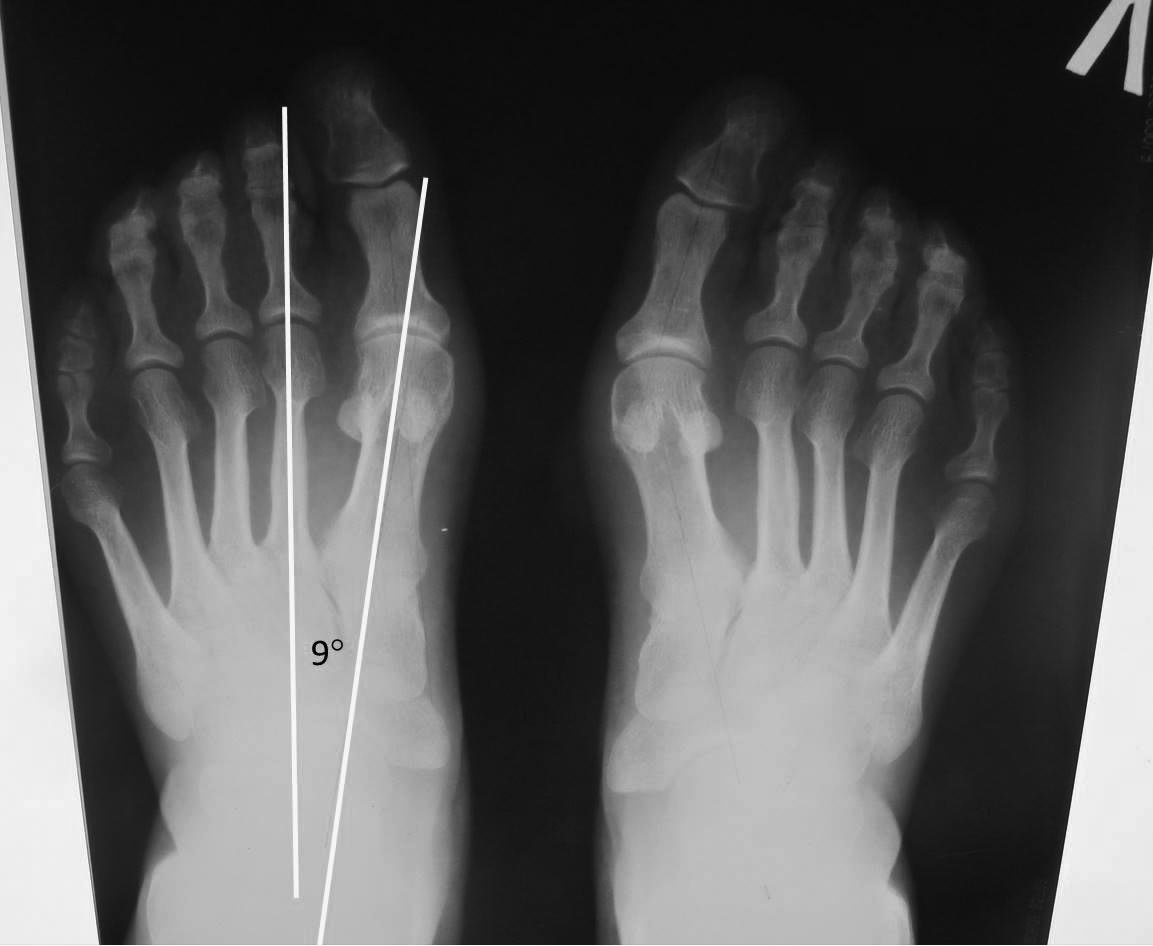

Уважаемые коллеги! Не знаю, найдет ли отклик этот пост? Долго сомневался, выкладывать ли случай на форум. Но уж больно необычный. Даже со скидкой на реалии сегодняшней жизни. Пациентка оперирована 6 мес назад в одной из московских ГКБ. С ее слов, обратилась с болями, характерными для болезни Мортона правой стопы. Была госпитализирована по ОМС. Как и положено, все было сделано бесплатно за исключением винтов (60 тыс.). Кроме удаления невромы были выполнены остеотомии scarf первых плюсневых, остеотомии пятых плюсневых и операции Гомана на четвертых пальцах. В диагнозе, правда, ничего о болезни портных и деформации 4-х пальцев не говорится. Наверное, это можно объяснить повседневной замотанностью и бумажной рутиной. Но как объяснить выполнение остеотомии scarf при величине первого межплюсневого угла 9 гр? И удаление невромы Мортона со стопы, которая не болела? На мой вопрос, как же она согласилась оперировать вторую стопу, пациентка ответила, что о второй ей сказали уже во время операции (спинальная анестезия), когда она была в полусонном от премедикации состоянии. И объяснили тем, что при УЗИ неврома была выявлена и на другой стопе и все равно рано или поздно заболела бы. Возможно, и невроме Мортона на другой стопе существует объяснение. Перепутали стопу, и пришлось искать аргументы. Но scarf при 9 гр… При том, что отклонение первого пальца кнаружи на одной стопе сохранилось. Сейчас пациентка испытывает сильные боли в стопах, длительное время нетрудоспособна. Я-то ей только один сильно торчащий винт удалил из 5 плюсневой. А чем еще помочь, кроме как психологически, не знаю.

Не знаю может у меня неправильный транспортир, но угол получился по этим снимкам больше чем 9. Судя по контрольным снимкам ничего катастрофического нет. Да слева тоже стоило сделать остеотомию по Эйкин. Жаль нет фотоснимков ног до операции, чтобы сравнить стоило ли так усердствовать. По поводу отеков стоп до 3 месяцев- у меня такое тоже бывало, ничего - проходили.Насчет того, что до операции не обсудили с пациенткой объем операции, не рассказали о длительности реабилитации- да- это серьезнейшая ошибка, о чем, если не путаю, в Вашей диссертации, Сергей Юрьевич, говорится. Также непонятна операция на бессимптомной по невроме ноге. Насчет сохраняющихся болей, нетрудоспособности- тут очень многое зависит от психотипа пациента- некоторые даже после очень удачно сделанных операций, ноют, недовольны и т.д. Тут уж действительно надо быть психотерапевтом.

Транспортир правильный, не сомневайтесь. Разница в измерениях углов очень частое явление. В мае я даже читал доклад на одной из конференций на эту тему. Предварительно попытался провести опрос на форуме с просьбой определить величину угла М1М2 на 4-х простых рентгенограммах (пост от 06 апреля, http://weborto.net/forum/1428264407/index_html). Большого интереса опрос не вызвал, но на почту 18 ответов все-таки получил, за что участникам большое спасибо. Так вот, разница в измерениях достигала 40-50%. На эту тему много работ написано. Но даже если не 9 гр., а 11-12. Разве это достаточный повод для остеотомии scarf? Иногда за одну неделю мне приходится делать по 4-5 повторных операций. И всяких «ужасов» мог бы показать. «Ужас» же этой ситуации в том, что остеотомии сделаны прекрасно. Только зачем? По поводу отеков стоп тоже согласен. Не только у Вас они бывают, но и у многих пациентов. И если на фоне отека пациент ходит, занимается физкультурой – это нормально. А если преимущественно лежит и страдает от болей, да еще гипертрофические рубцы формируются – тогда это уже осложнение.